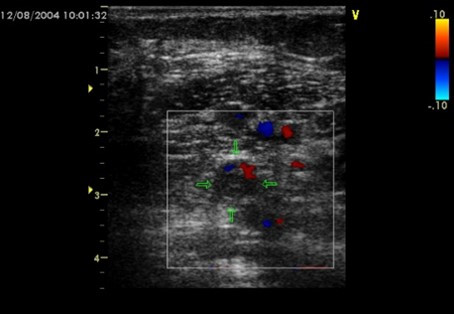

下肢の血管に超音波をあてると、このようにエコー画像では映し出されます。(違いがわかりやすいよう、血の流れている部分に色をつけています。)

左の健常な方に比べ、右の方には、ほぼ色がないことから、血の流れが止まっているほどに遅いことがわかります。このことから、大きな血液の塊の血栓ができて重度の血管の詰まりになっていることが疑われます。